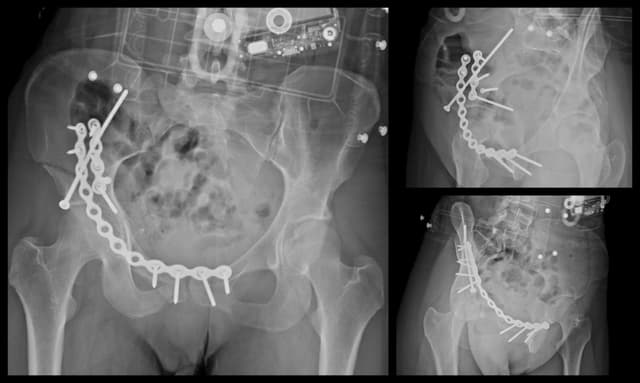

Anterior Column Acetabulum ORIF

Post-op